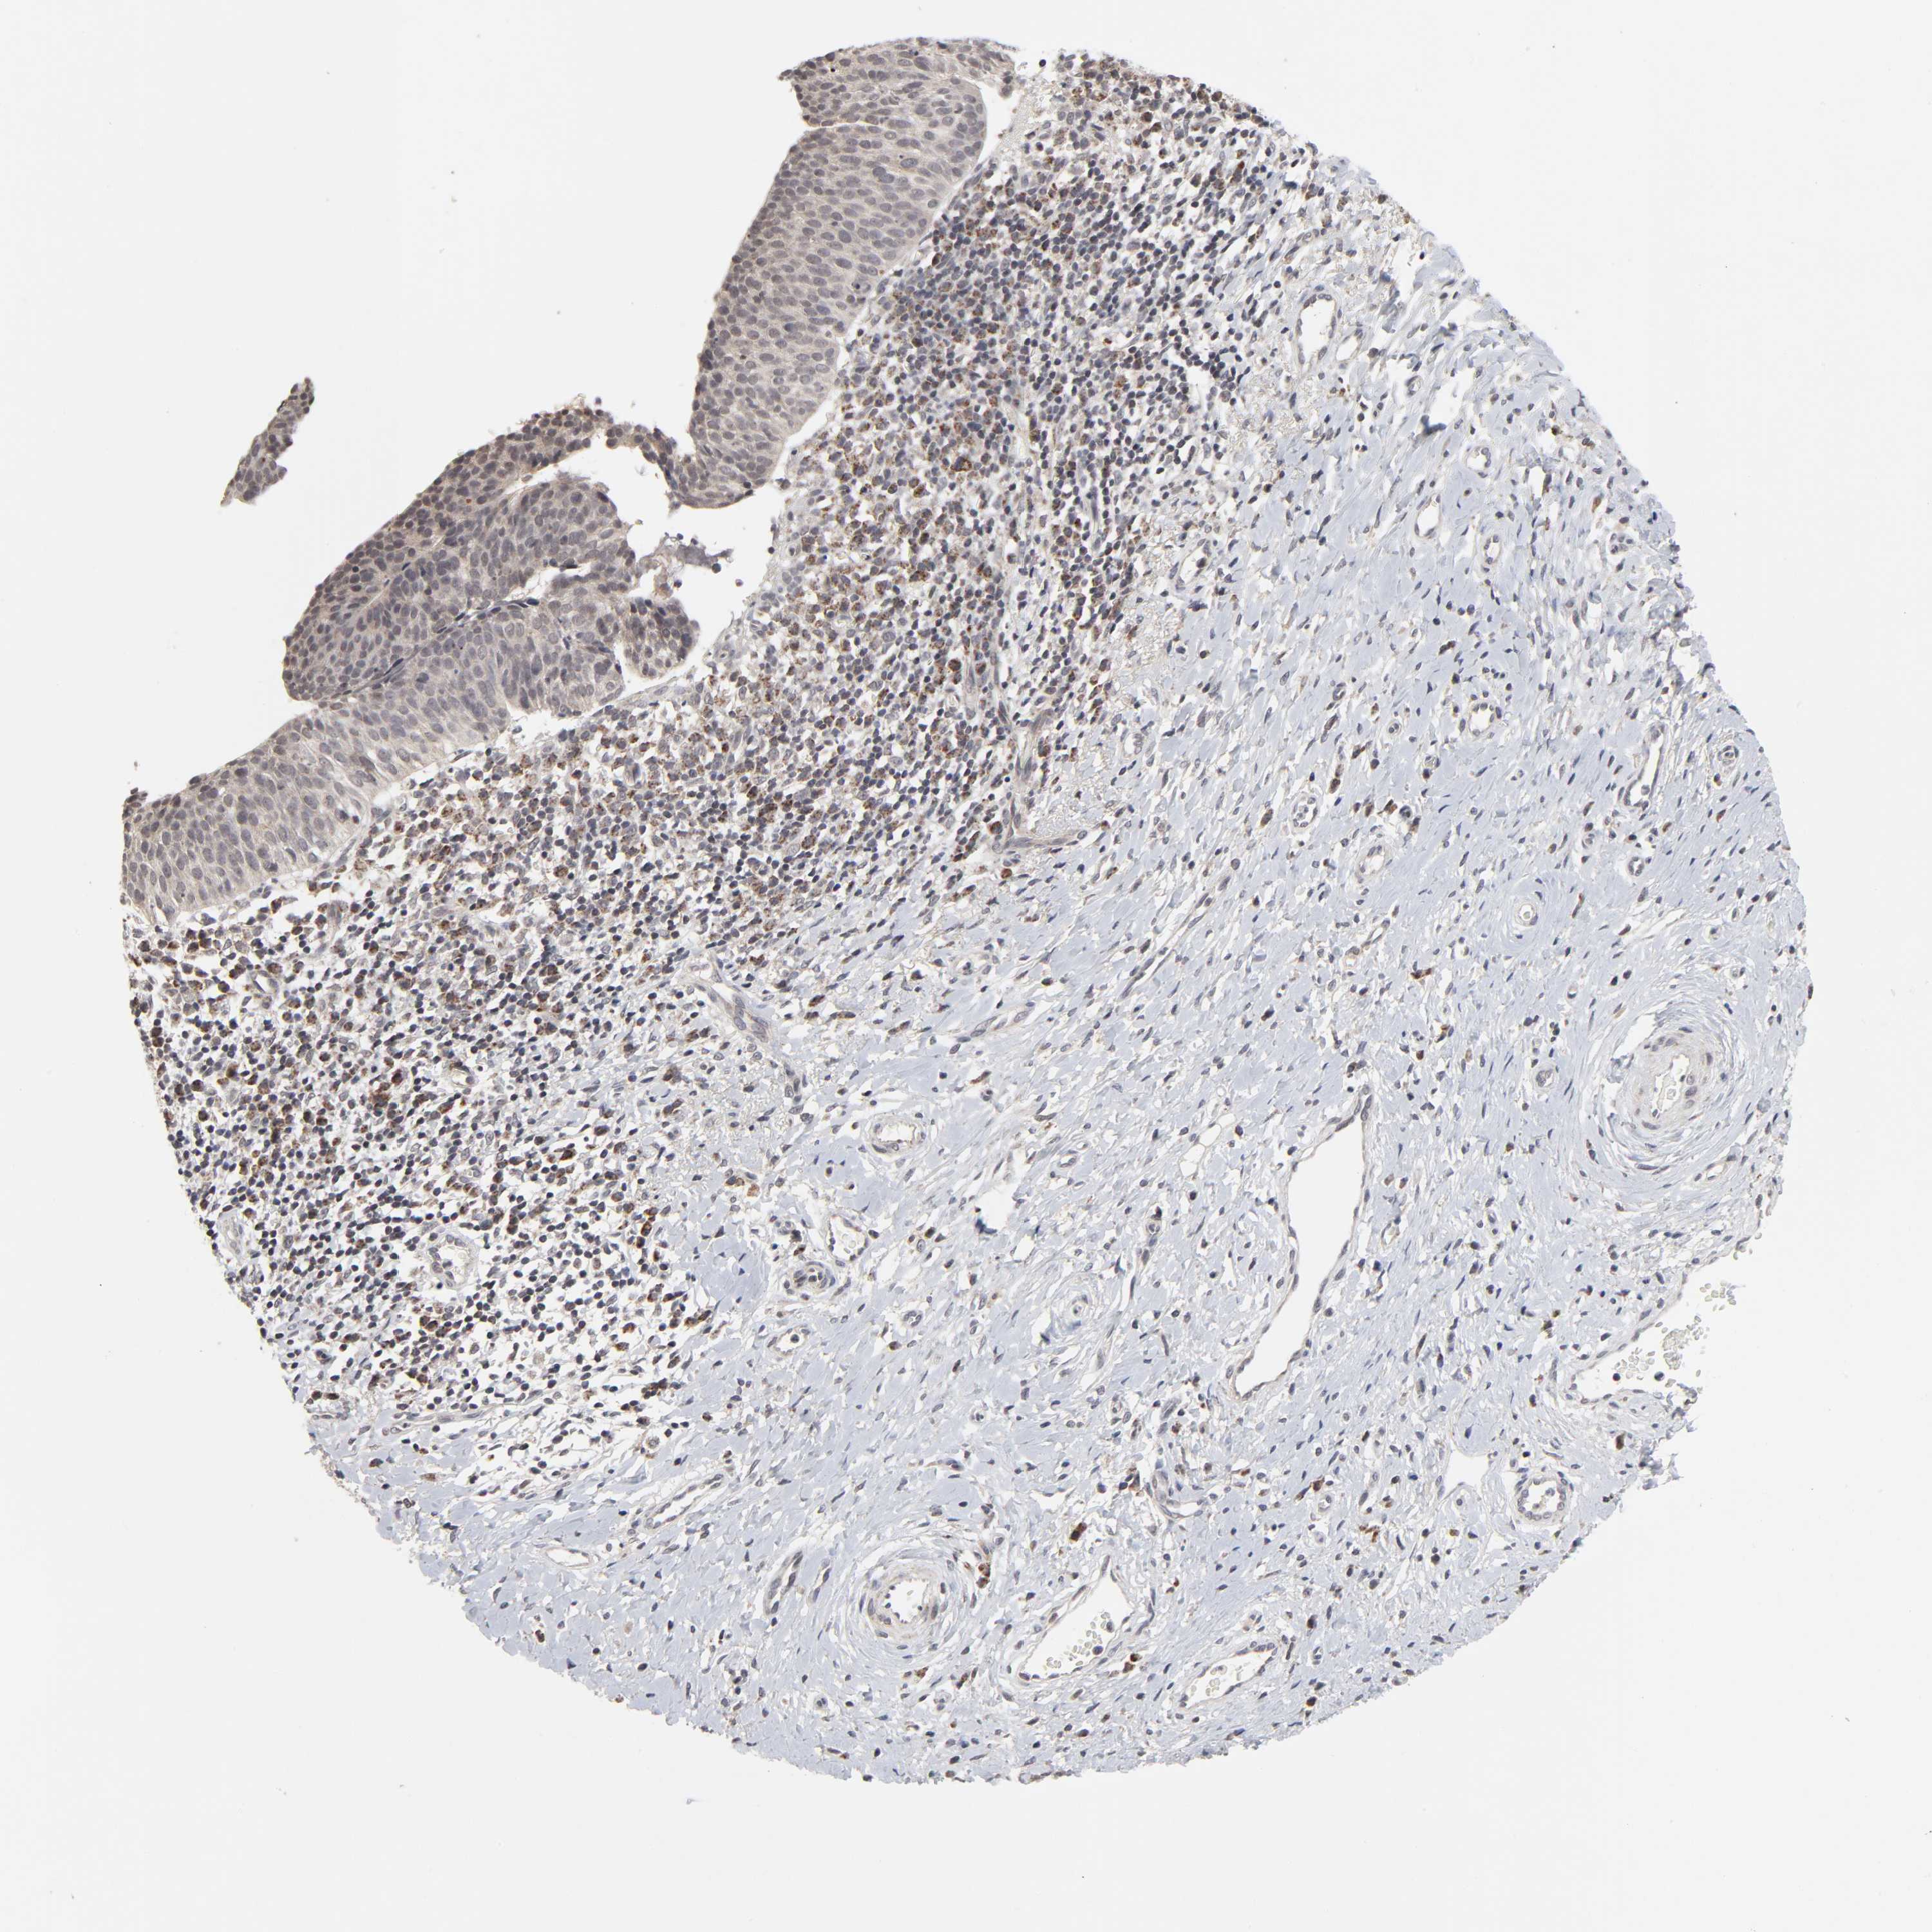

CERVICAL CANCER - Protein expressioni

A mouse-over function shows sample information and annotation data. Click on an image to view it in a full screen mode. Samples can be filtered based on level of antibody staining by selecting one or several of the following categories: high, medium, low and not detected. The assay and annotation is described here.

Note that samples used for immunohistochemistry by the Human Protein Atlas do not correspond to samples in the TCGA dataset.

Antibody stainingi

Antibody staining in the annotated cell types in the current human tissue is reported as not detected, low, medium, or high, based on conventional immunohistochemistry profiling in selected tissues. This score is based on the combination of the staining intensity and fraction of stained cells.

Each image is clickable and will lead to virtual microscopy that enables deeper exploration of all samples and also displays staining intensity scores, fraction scores and subcellular localization as well as patient and tissue information for each sample.

Antibody HPA004171

Staining

High

Medium

Low

Not detected

Intensity

Strong

Moderate

Weak

Negative

Quantity

>75%

75%-25%

<25%

None

Location

Nuclear

Cytoplasmic/membranous

Cytoplasmic/membranous,nuclear

Squamous cell carcinoma, NOS

Adenocarcinoma, NOS